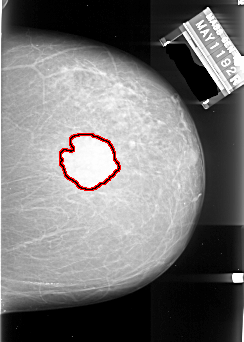

A_1004_1.LEFT_CC

FILE: A_1004_1.LEFT_CC.OVERLAY

TOTAL_ABNORMALITIES 1

ABNORMALITY 1

LESION_TYPE MASS SHAPE IRREGULAR MARGINS SPICULATED

ASSESSMENT 5

SUBTLETY 5

PATHOLOGY MALIGNANT

TOTAL_OUTLINES 2

BOUNDARY

CORE